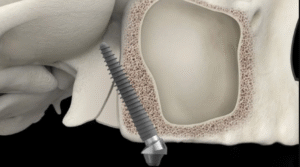

Nha Khoa Đông A với sự tham gia điều trị của Bác sĩ CKI Cang Hồng Thái, chuyên gia có hơn 20 năm kinh nghiệm trong lĩnh vực cấy ghép nha khoa, phục hình răng và nha khoa thẩm mỹ.

Trong quá trình điều trị, Bác sĩ Cang Hồng Thái luôn lắng nghe và hiểu rõ nhu cầu của bệnh nhân, đồng thời giúp giải quyết các vấn đề tâm lý mà bệnh nhân đang gặp phải. Mọi phương án điều trị được thiết kế sao cho ít xâm lấn gây tổn thương cho răng thật, mô mềm và xương hàm nhất có thể, để mang lại trải nghiệm điều trị răng miệng tốt nhất cho bệnh nhân.

Bác sĩ Chuyên khoa I Cang Hồng Thái hiện là Giám đốc Nha Khoa Đông A và có hơn 20 năm kinh nghiệm trong lĩnh vực cấy ghép Implant, chỉnh nha, phục hình răng thẩm mỹ. Ông đã làm việc tại các bệnh viện lớn như Răng Hàm Mặt và Đại học Y Dược TPHCM.